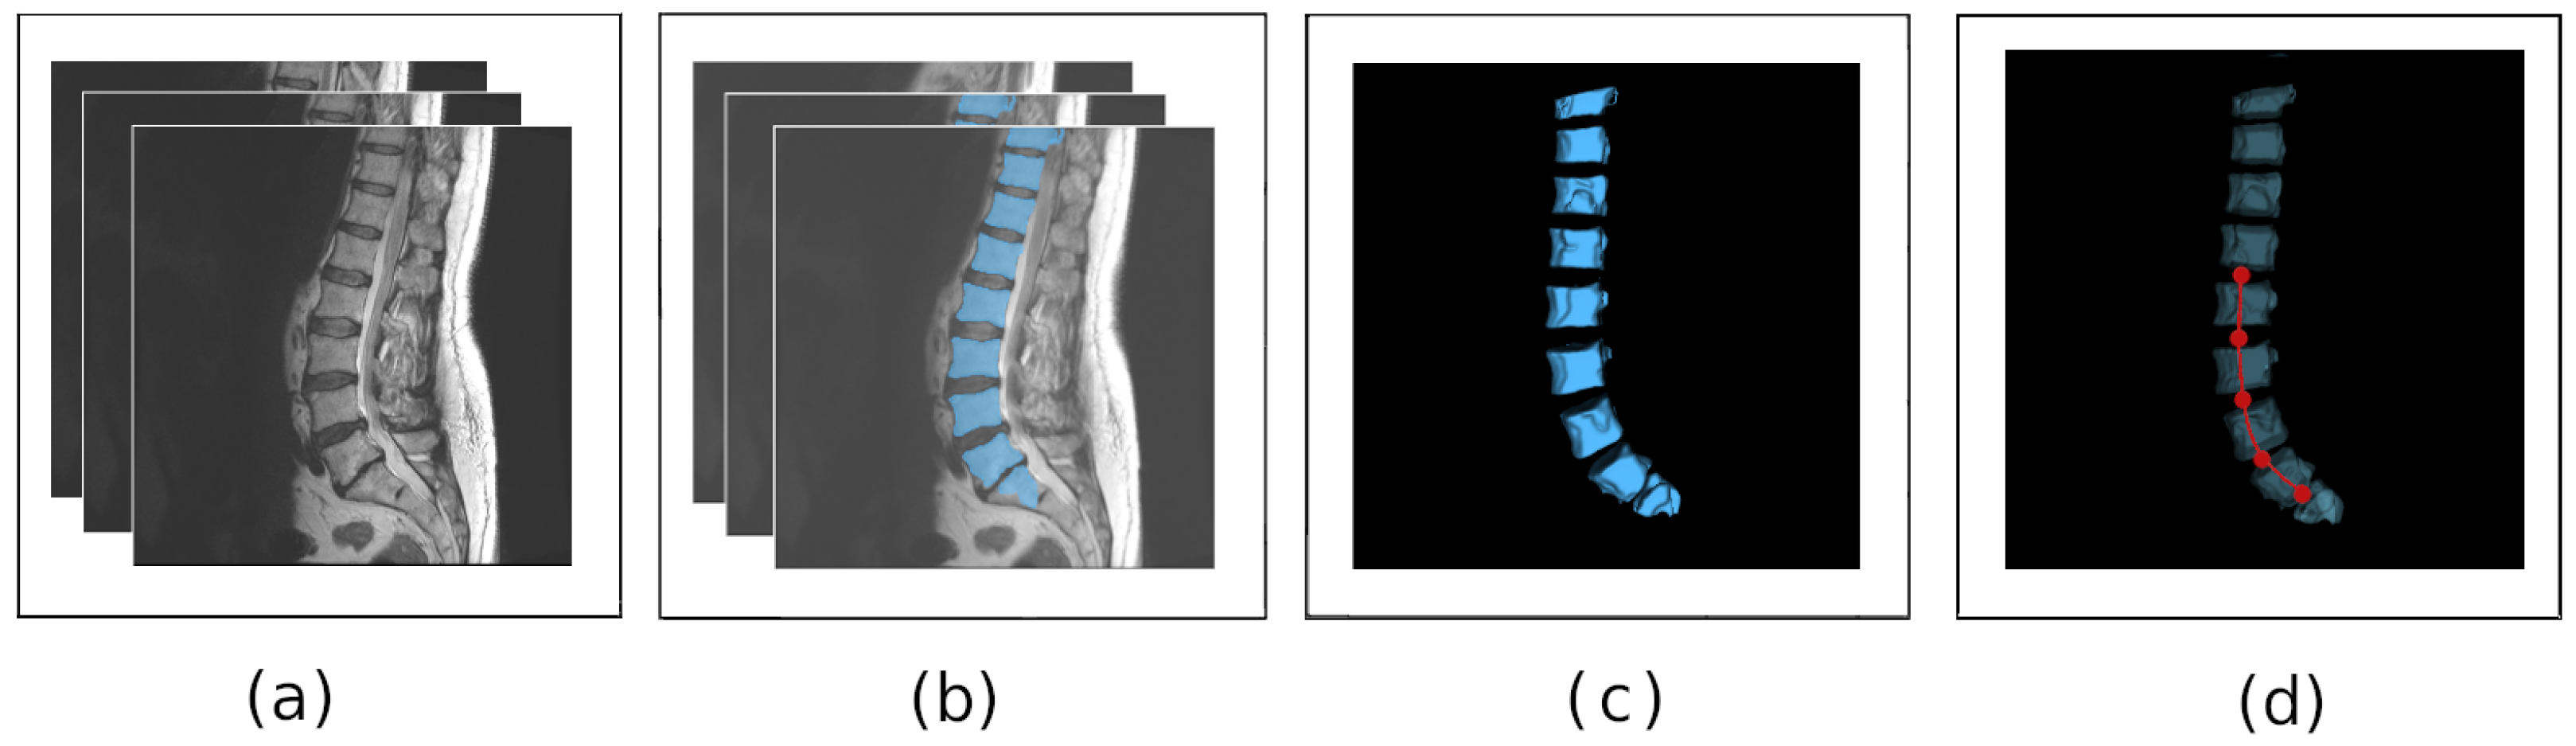

2.1. Lordosis Curve Extraction from Medical Data

3.1. Segmentation of Vertebral Bodies from Medical Data